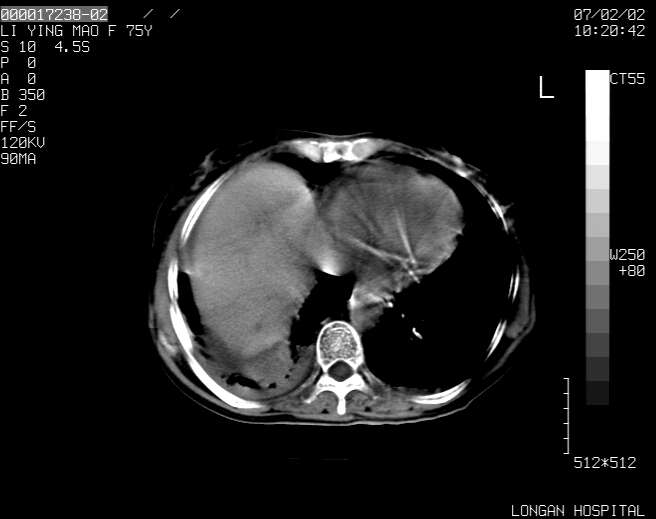

以下是引用dyqct在2007-2-10 8:53:00的发言:[br]考虑:1、肝脏多发囊肿[br] 2、左肾囊肿,右肾多发结石并积水。[br] 3、右胸少量积液。[br] 4、右肾周包裹性积液或淋巴管瘤(有见缝就钻的征象、薄隔、小结节状钙化)?[br] 5、腰椎动脉瘤样骨囊肿?[br] [br] [br]